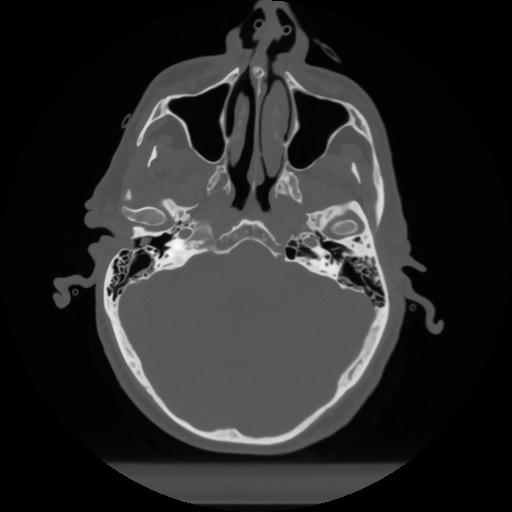

12 P.BLANDAS,,Vol,0.5,P.BLANDAS,,